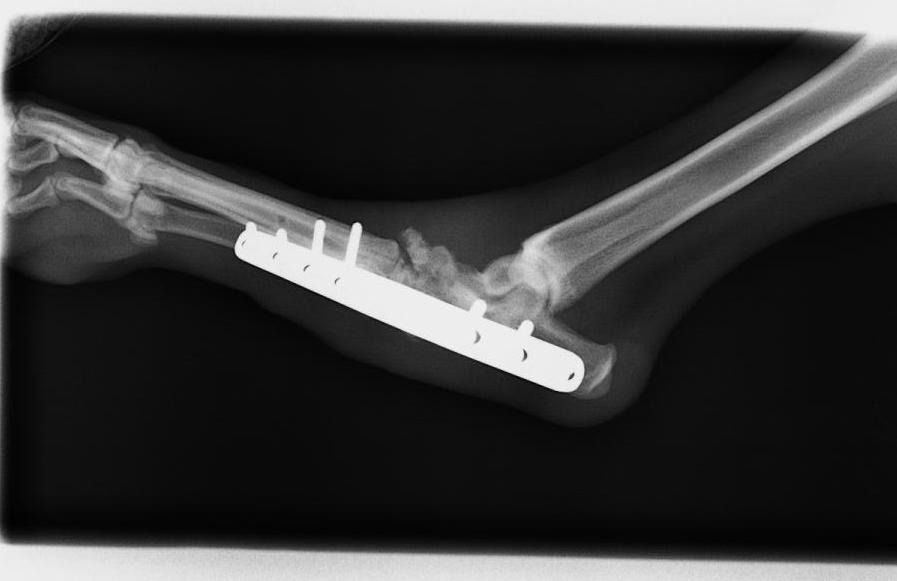

Artrodesis

Es una cirugía que consiste en fusionar articulaciones que tienen problemas de inestabilidad, dolor o artrosis, para eliminar el dolor y tener una buena funcionalidad y calidad de vida.

Se colocan placas especiales con tornillos, que adaptados a la forma que queremos que la articulación adopte una vez fusionada.